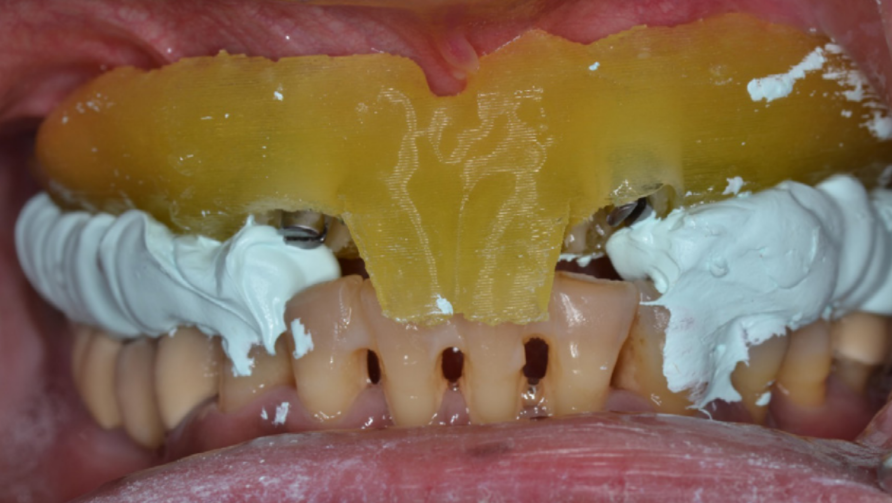

Щоб записати висоту прикусу, вже визначену негайним протезом, металеві штирі було видалено з шаблону та шаблон для навігаційної хірургії було надійно закріплено на серединних імплантах, з використанням модифікованих тримачів для імплантів. (зображення 9)

Збережені центральні різці на шаблонні виконували роль переднього затримувача для правильного передньо-заднього розміщення нижньої щелепи.

Перші моляри на шаблонні допомогли відтворити встановлений вертикальний вимір прикусу.

Хоча серединна частина молярів була видалена зі шаблону, щоб полегшити встановлення імплантів, дистальна частина зубів функціонально відповідала вимогам збереження правильного прикусу.

Щоб полегшити процес проведення цієї процедури, матеріал для зняття прикусу (Prestige Bite, Vanini, Італія), було застосовано для подальшої стабілізації центрального змикання щелеп (CR) на визначеній висоті прикусу. (зображення 10)